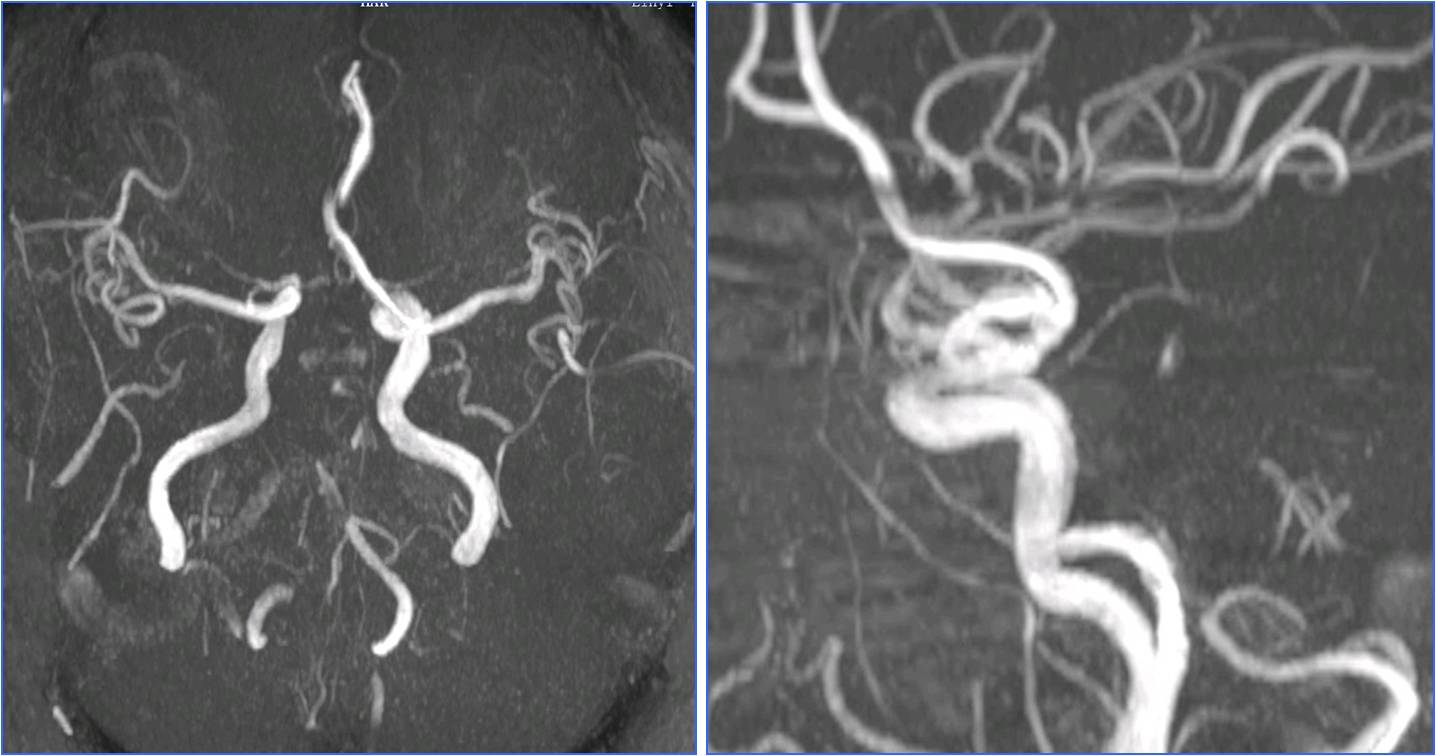

》11:56头MRA。

▼11:56头MRA

▼4天后复查MRA

▼术前头MRA

▼术后24小时头MRA